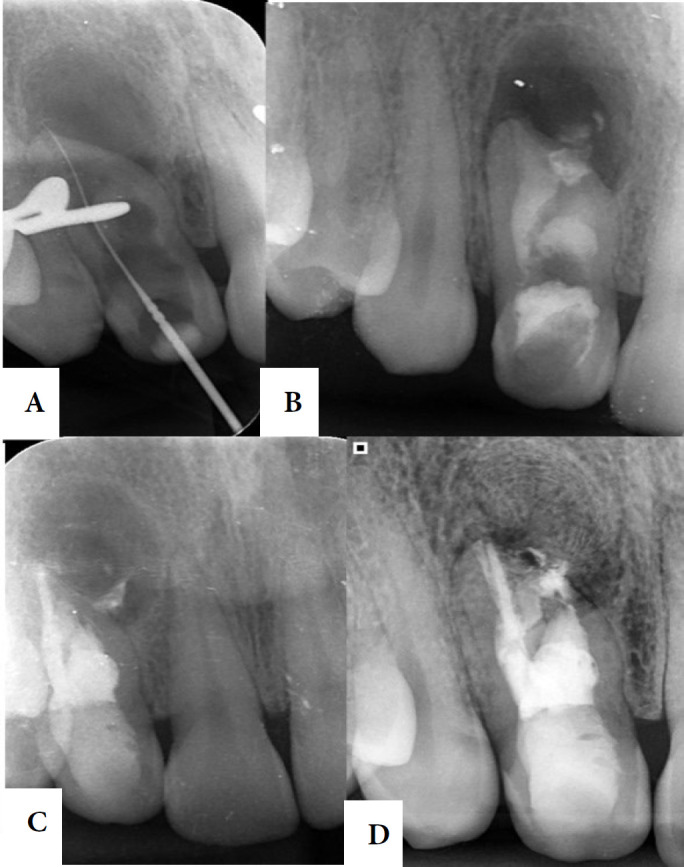

Dens invaginatus (DI) is one of the developmental dental anomalies that results in an invagination of the enamel organ into the dental papila during odontogenesis. The purpose of this study is to report a case of nonsurgical endodontic treatment of an Oehlers type II DI in a right maxillary lateral incisor with an extensive periapical damage, along with the two-year clinical and tomographic follow-up. A 30-year-old patient was referred for endodontic treatment of tooth #12. On clinical examination, a change in the shape and color of the crown was observed. The tooth responded negative to pulp sensibility, percussion, palpation and mobility tests. After tomographic evaluation, an Oehlers type II DI was visualized, in addition to an extensive periradicular lesion. The diagnosis was asymptomatic apical periodontitis. The treatment was carried out in two sessions, through intense enhancement of the auxiliary chemical substance with passive ultrasonic irrigation, XP-Endo Finisher and the use of hydroxide-based intracanal medication. Appropriate treatment in cases with anatomic variations requires an accurate and early diagnosis based on clinical examination and radiographic images. A two-year follow-up of the present case showed that the correct diagnosis associated with appropriate instrumentation techniques, supplementary disinfection, and adequate three-dimensional sealing of the canal with filling material, resulted in regression of the periradicular lesion and bone repair.